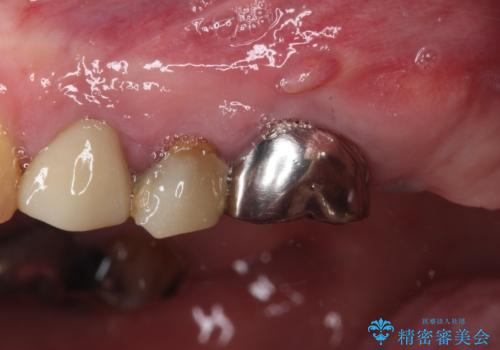

治療を開始したところ、上顎は排膿路が消失し、症状も落ち着きましたが、下顎は一向に改善されませんでした。

改めて診療を行ったところ、歯根破折が認められ、抜歯後にインプラント治療を行うこととしました。